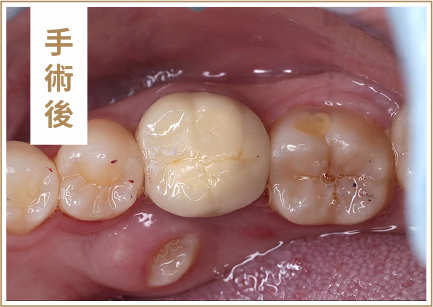

杜牙根後牙齒的剩餘結構較少,牙齒變得脆弱容易斷裂。

牙冠可以提供額外的保護,防止牙齒崩裂。